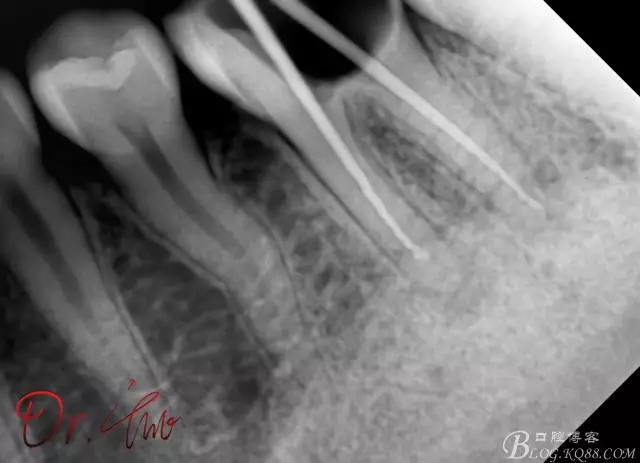

最后根充,明顯可看到臺階位置,期待預(yù)后效果

640.webp (11).jpg